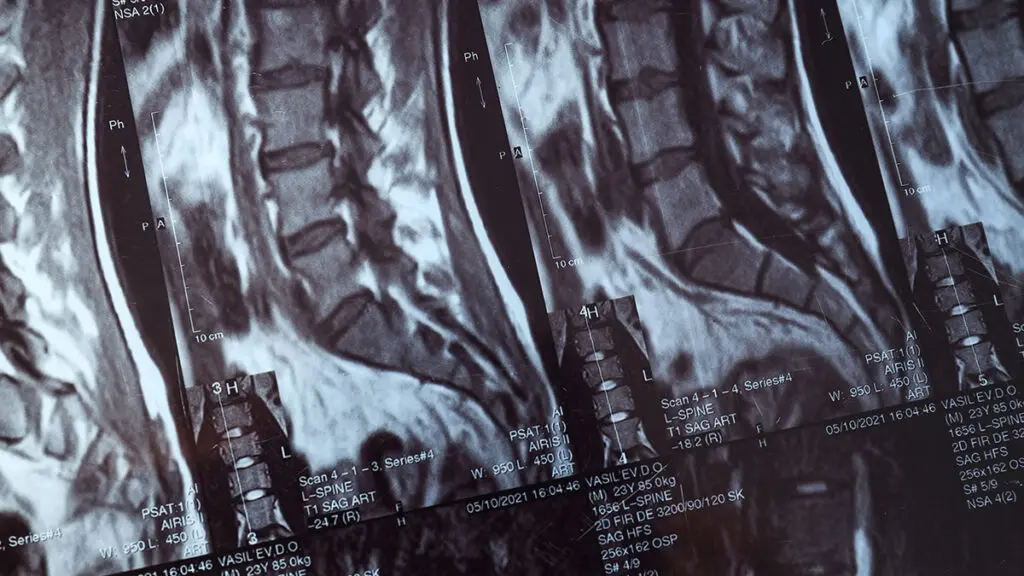

La microdiscectomia ernia del disco è una delle procedure neurochirurgiche mininvasive più eseguite al mondo per il trattamento dell'ernia del disco sintomatica. Global Spine Solutions offre a Roma percorsi completi per microdiscectomia ernia del disco: dalla diagnosi strumentale accurata alla pianificazione pre-operatoria, fino all'intervento vero e proprio e alla riabilitazione post-operatoria.

I neurochirurghi di Global Spine Solutions specializzati in microdiscectomia ernia del disco adottano un approccio mininvasivo che consente di ridurre al minimo il trauma muscolare, limitare la perdita di sangue e accelerare i tempi di recupero. In molti casi, il ricovero si riduce a 24-48 ore con ritorno alle attività leggere entro 2-4 settimane dall'intervento.